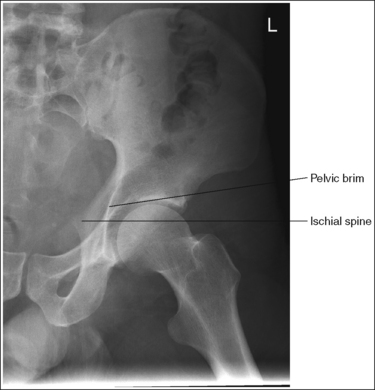

• Detecting pelvis rotation. Rotation on an AP hip projection is initially detected by evaluating the relationship of the ischial spine and the pelvic brim, the alignment of the sacrum and coccyx with the symphysis pubis, and the degree of obturator foramen demonstration. If the patient was rotated toward the affected hip, the ischial spine is demonstrated without pelvic brim superimposition, the sacrum and coccyx are not aligned with the symphysis pubis but are rotated away from the affected hip, and the obturator foramen is narrowed (see Image 1). If the patient has been rotated away from the affected hip, the ischial spine is not aligned with the pelvic brim but is demonstrated closer to the acetabulum, the sacrum and coccyx are not aligned with the symphysis pubis, but are rotated toward the affected hip, and the obturator foramen is widened (see Image 2).

IMAGE 1

IMAGE 2

The ischial spine is demonstrated without pelvic brim superimposition, the sacrum and coccyx are not aligned with the symphysis pubis but are rotated away from the affected hip, and the obturator foramen is narrowed. The patient was rotated toward the affected hip. The femoral neck is foreshortened, and the lesser trochanter is demonstrated in profile. The patient's leg was externally rotated.

Rotate the patient away from the affected hip until the ASISs are positioned at equal distances from the imaging table. Internally rotate the patient's leg until the foot is angled 15 to 20 degrees from vertical and the femoral epicondyles are positioned parallel with the imaging table, as shown in Figure 7-4.

The ischial spine is not aligned with the pelvic brim but is demonstrated closer to the acetabulum, the sacrum and coccyx are not aligned with the symphysis pubis but are rotated toward the affected hip, and the obturator foramen is clearly demonstrated. The patient was rotated away from the affected hip (left posterior oblique [LPO] position).

Rotate the patient toward the affected hip until the ASISs are positioned at equal distances from the imaging table.